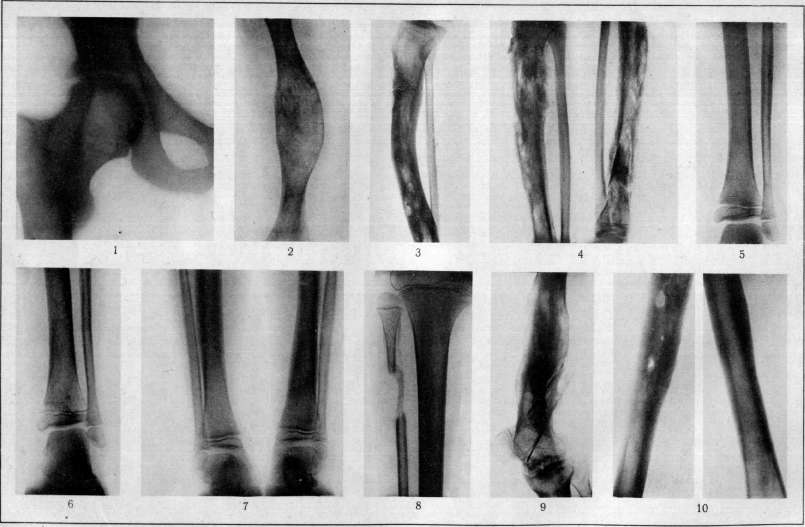

Рентгенография позволяет обнаружить секвестры и участки деструкции, зоны остеопороза и остеосклероза, а также деформацию концов костных фрагментов. При огнестрельном остеомиелите на рентгеновских снимках видны металлические осколки, застрявшие в мягких тканях. Другие диагностические методы позволяют более подробно исследовать пораженную область и выявить причины гнойных процессов.